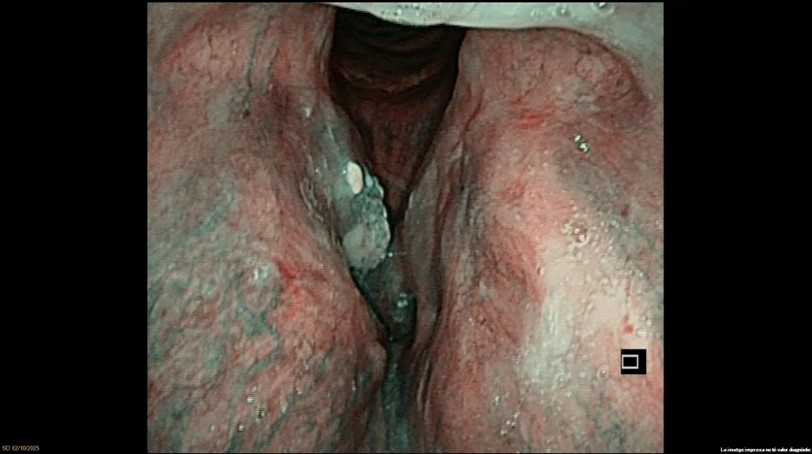

Exophytic lesion on the right vocal cord. NBI suspicious for malignancy. Laryngeal dysplasia. Ventricle and AC appear clear. Motility preserved

MTB: explain the need for an excisional biopsy and treatment options

Plan: TOLMS microlaryngoscopy